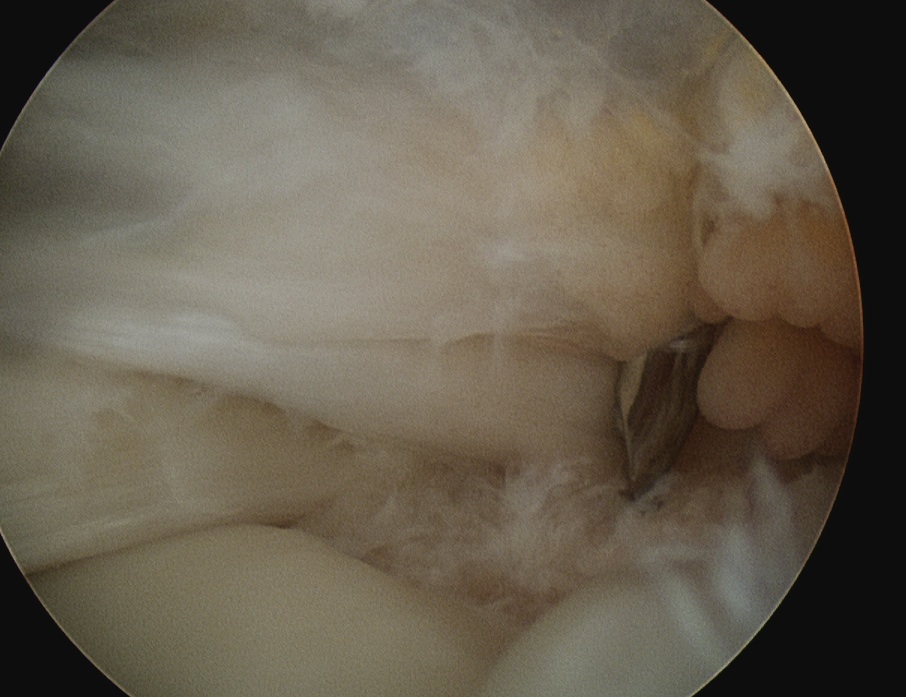

Assess tendon mobilisation / tear geometry

- perform releases if needed

- as per open surgery

- above and below tendon 1 cm medial to glenoid

- release coracohumeral ligament

Large U shaped tendon

- insert margin convergence sutures

- put camera in lateral portal

- insert posterior cannula over switching stick

- anterior and posterior bird beaks